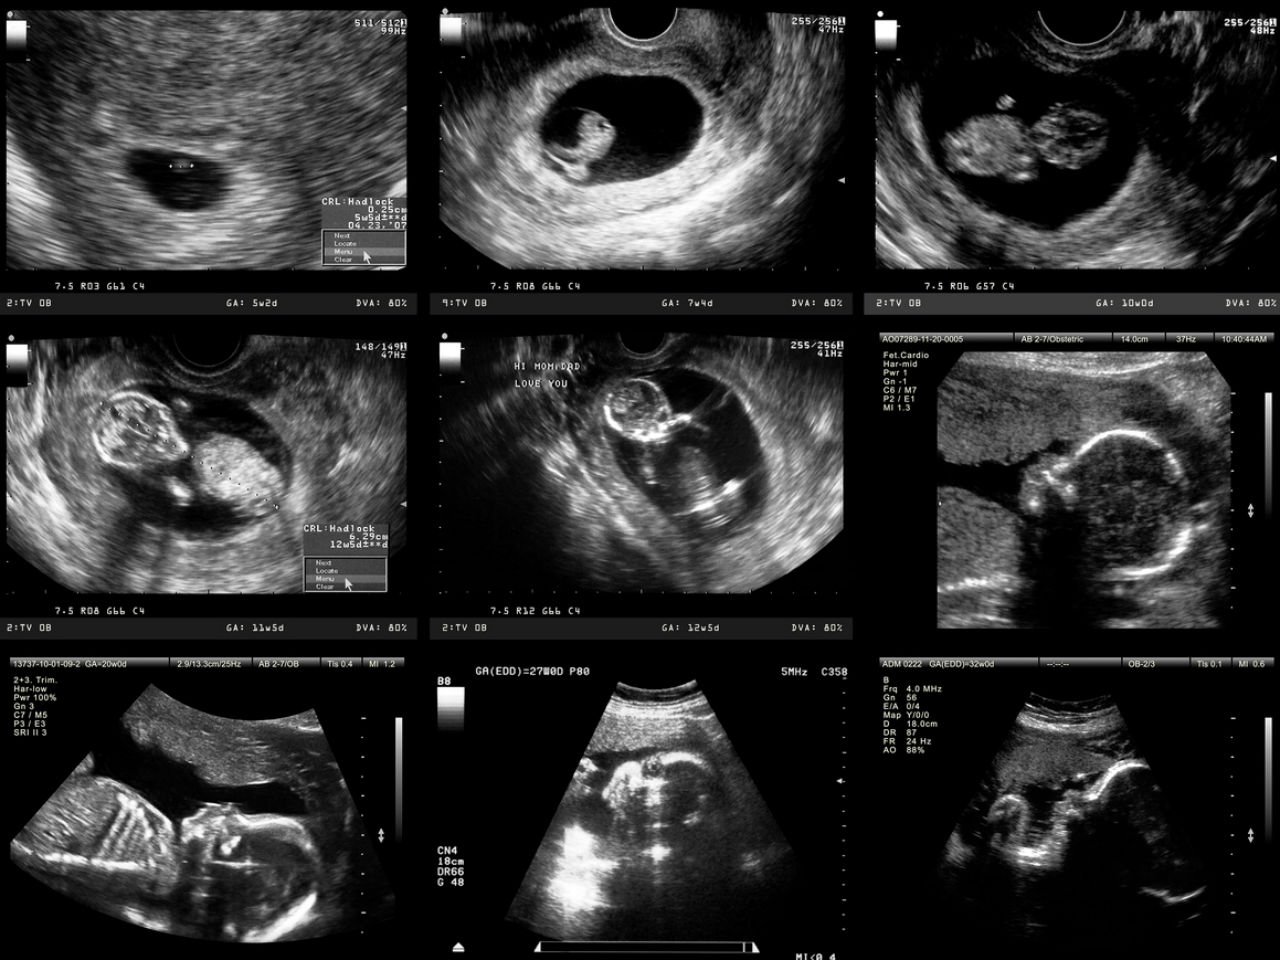

Week By Week Ultrasound Gallery - 2D 3D 5D Visual Pictures

viewamiracle.comFirst Ultrasound Shows I’m 3 Weeks Behind | BabyCenter

viewamiracle.comFirst Ultrasound Shows I’m 3 Weeks Behind | BabyCenter

alai-web.orgWeek By Week Baby Ultrasound | Surrogacy India

alai-web.orgWeek By Week Baby Ultrasound | Surrogacy India

kiranivfgenetic.comultrasound pregnancy

kiranivfgenetic.comultrasound pregnancy